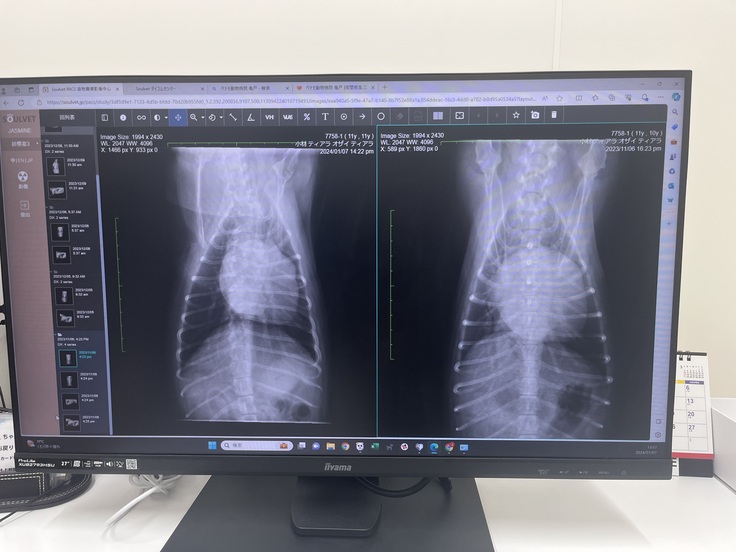

レントゲン、エコー、血圧の検査結果から

問題無く順調に回復しておりました✨

心臓もかなり小さくなり

僧帽弁、三尖弁共に軽度の逆流は残るものの

※レントゲン、エコーの写真は

左側が術後で、右側が術前になります。